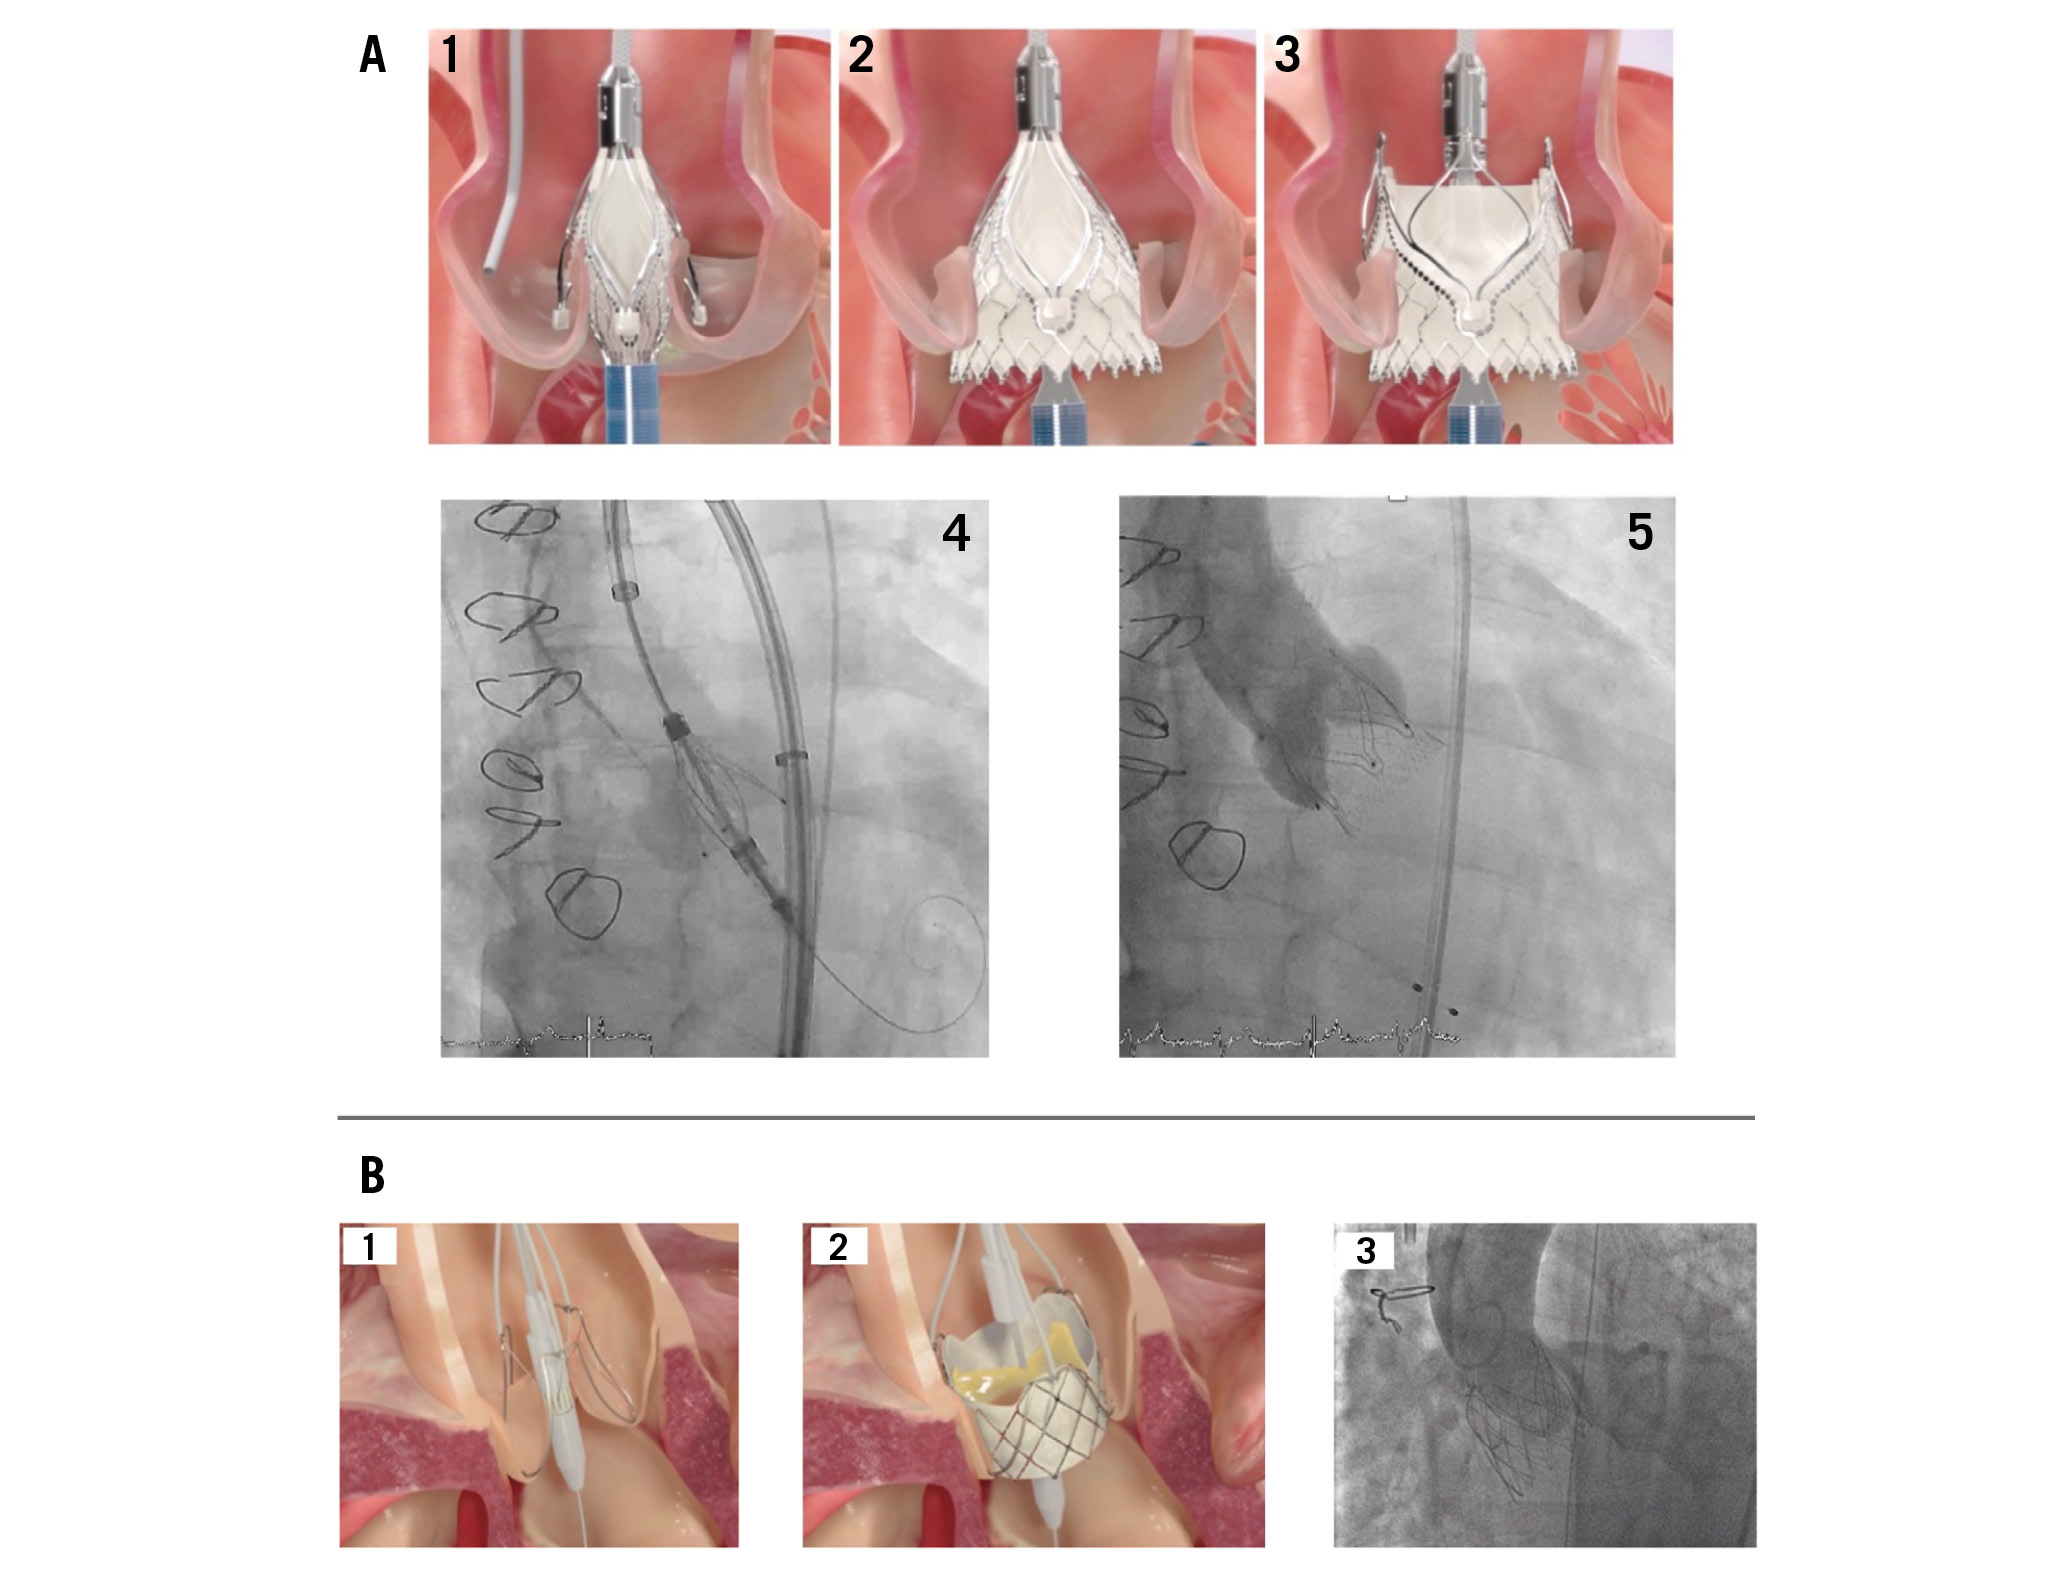

The self-expanding bioprosthesis consists of a nitinol frame with 3 porcine pericardial valve leaflets (Figure 7). The unique feature of the Trilogy valve is the locator technology which provides perfect positioning in the native valve and safe anchoring in the annulus39. The 3 radial locators are positioned under fluoroscopy or transoesophageal echocardiography in each aortic root sinus, and thus, commissural alignment can be reliably achieved54. Coronary access is further facilitated by 3 large open cells at the top of the prosthesis. The technology also limits deep implantation and therefore decreases the risk of protrusion into the LVOT or migration into the left ventricle. Additionally, a “natural” paravalvular seal results during the final deployment step, with the locators clipping onto the native leaflets and pinching them to the stent frame (Figure 7).

The Trilogy device is advanced through an 18 Fr, 85 cm long preshaped introducer sheath that extends through the aortic arch. The delivery system includes a feature to rotate the valve to allow commissural alignment of the locators and engagement with each cusp (Figure 8). The prosthesis is available in 3 sizes (23 mm, 25 mm, and 27 mm) which allows treatment of annular diameters up to 28.6 mm39.

Figure 8. Deployment of transcatheter heart valves. A) Deployment of the Trilogy THV: 1. Locators align the THV with the native cusps; 2. Inflow is deployed, with limited protrusion; 3. Outflow is deployed: locators “clip” onto native leaflets, forming a seal and stable securement; 4. THV with locators spread during implantation, seating the locators in the sinuses; 5. Valve after implantation with secure anchoring and no paravalvular regurgitation. B) Deployment of the J-Valve THV: 1. Anchor rings grasp the native leaflets in correct anatomical alignment; 2. The THV is deployed, anchoring in the annulus; 3. The THV after implantation with full expansion and no aortic regurgitation. THV: transcatheter heart valve

A similar anchoring concept to that used for the Trilogy prosthesis is used for the J-Valve. This prosthesis consists of 3 bovine pericardial leaflets in a self-expanding, low-profile nitinol frame with 3 U-shaped “anchor rings” (Figure 7). It is available in 5 sizes (22, 25, 28, 31, and 34 mm) to treat a wide range of anatomies, with an annular diameter of up to 33.1 mm.

The valve is advanced using an 18 Fr delivery system. The deployment is performed in 2 steps. First, the anchor rings are opened and advanced into the aortic sinuses for commissural alignment. Second, the THV frame is opened and cinched against the clasped native leaflets, leading to safe anchoring in the annulus58 (Figure 8).